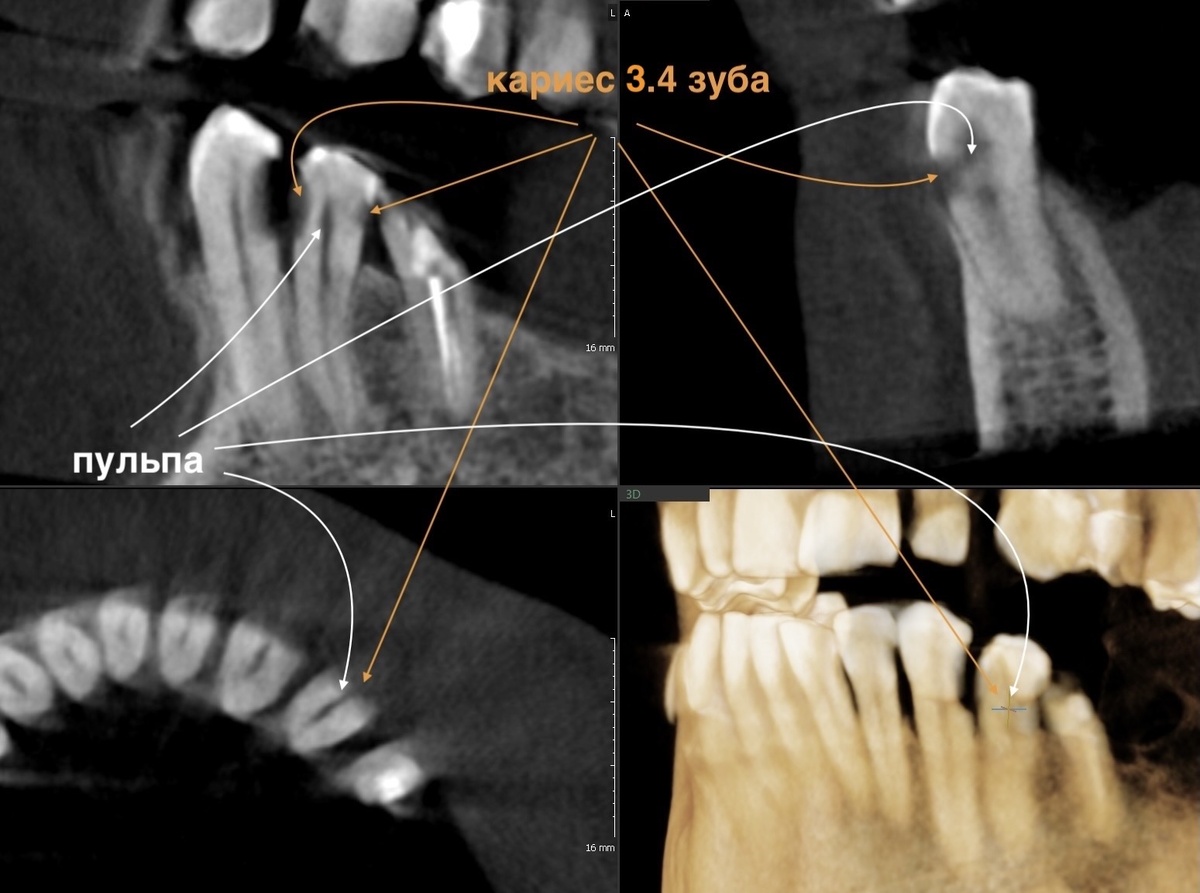

Вспомним старую компьютерную томограмму, ещё до лечения сделанную, самые экстремальные полости оценим:

Меньше миллиметра тканей отделяет кариозные полости от нерва. При таких глубоких поражениях многие депульпировали бы зубы "для надёжности".

И пациенты, часто, того же мнения придерживаются - надёжнее удалить нерв. Собственно, так и есть. Но есть врачи, которым под силу оставить зуб живым даже в такой сложной ситуации и делают они это на потоке. Для них это не чудо, а работа.

Вот и в данном случае, по прошествии 1 года и 8 месяцев, можно с уверенностью утверждать, что всё прошло успешно. Оценим свежие срезы (ноябрь 2025 года) КЛКТ, а сверху в коллаж я добавила фотографии полостей, которые были очищены от кариеса в феврале 2024 года (для оценки серьёзности ситуации):